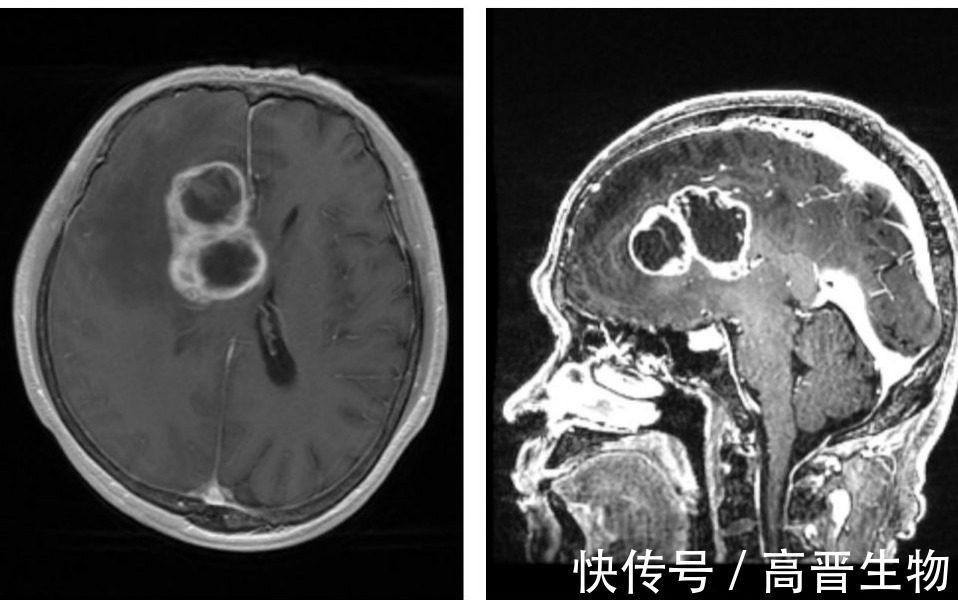

可能大多数人对胶质瘤比较陌生,虽然它不像其他肿瘤那般为人熟知,但胶质瘤的危害却是极大的。它属于一种恶性程度很高的脑部肿瘤,据统计,每年新发脑胶质瘤患者约10万人,年死亡人数约8-9万人。这其中,近一半患者都属于胶质母细胞瘤(glioblastoma multiforme,GBM)。GBM患者5年生存率仅有5.6%,是常见癌症中五年生存率最低的。患者确诊GBM之后的生存期一般只有13-15个月。

GBM无疑是抗癌领域最难攻克的一道关卡。由于其往往呈浸润性生长,与周围正常脑组织无明显边界,且可位于脑实质功能区,手术、传统放疗往往难以彻底清除,需要联合辅助治疗。此外,血脑屏障的存在,让普通抗癌药物难以抵达脑部发挥疗效。发病率较高,治疗药物匮乏,术后复发率也高的GBM,让人们迫切希望社会出现一种更为精准有效且副作用低的新型治疗方式。

硼中子俘获治疗(BNCT)作为一种新型的肿瘤辅助治疗方法,近年来不仅在中枢神经系统肿瘤,而且在头颈部肿瘤等其他肿瘤的治疗方面,都取得了许多令人振奋的成果。BNCT的核心原理是利用低能中子与亲肿瘤含硼药物发生核反应,在细胞范围内定点达到精准摧毁癌细胞,具有安全性高、定位精准、价格相对低廉等特点。

早年间,日本的研究者曾对200多个高级别胶质瘤患者使用BSH(用于临床试治的含硼药物)在手术中进行BNCT治疗。结论证明这比传统的光子束治疗要有效得多。其中2例胶质母细胞瘤和4例间变性星形细胞瘤的患者生存时间超过10年。之后瑞典在开展的临床试验中采用BPA(全球唯一上市的BNCT首荐药物)长时间注射治疗恶性胶质瘤,患者生存时间中位数达18个月。还有很多国家利用不同硼药对胶质瘤进行临床研究。